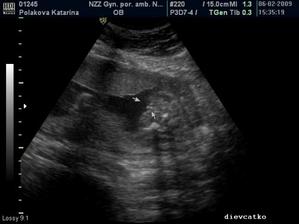

6.2.2009 - 20tt+5, 4D ultrazvuk - potvrdené! Cakame dievcatko - Sofia. Skontrolovane organy a vsetko ostatne, Sofinka je zdrava a vyvija sa tak ako ma 🙂 Vaha 345g, asi 20cm.